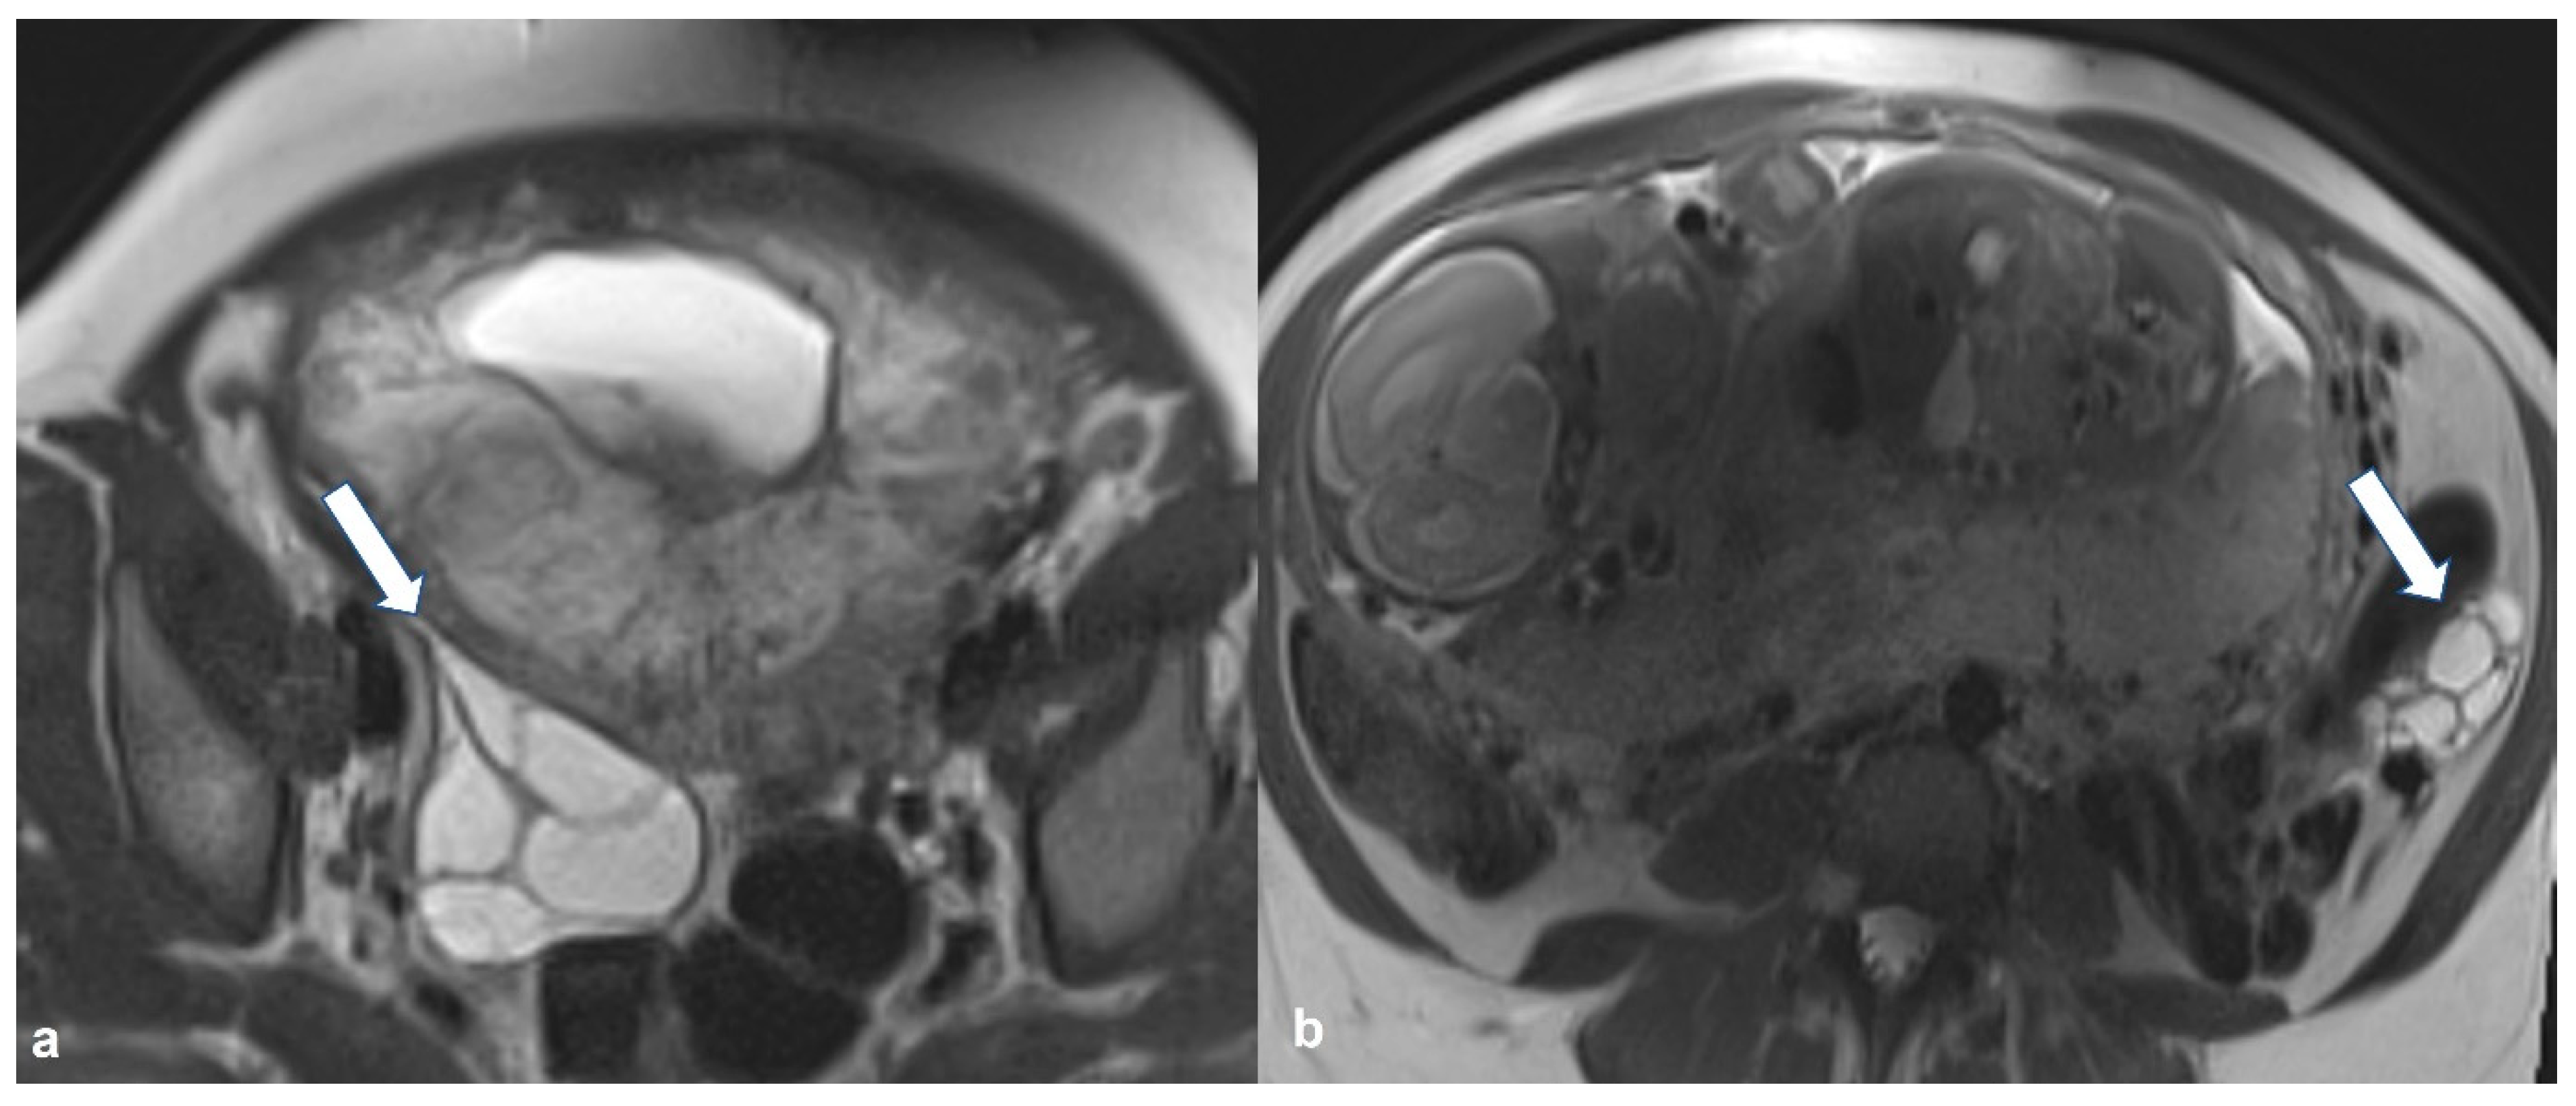

2.1.4. Endometrioid Carcinoma and Clear Cell Carcinoma

2.2. Benign Tumors That Can Mimic EOC